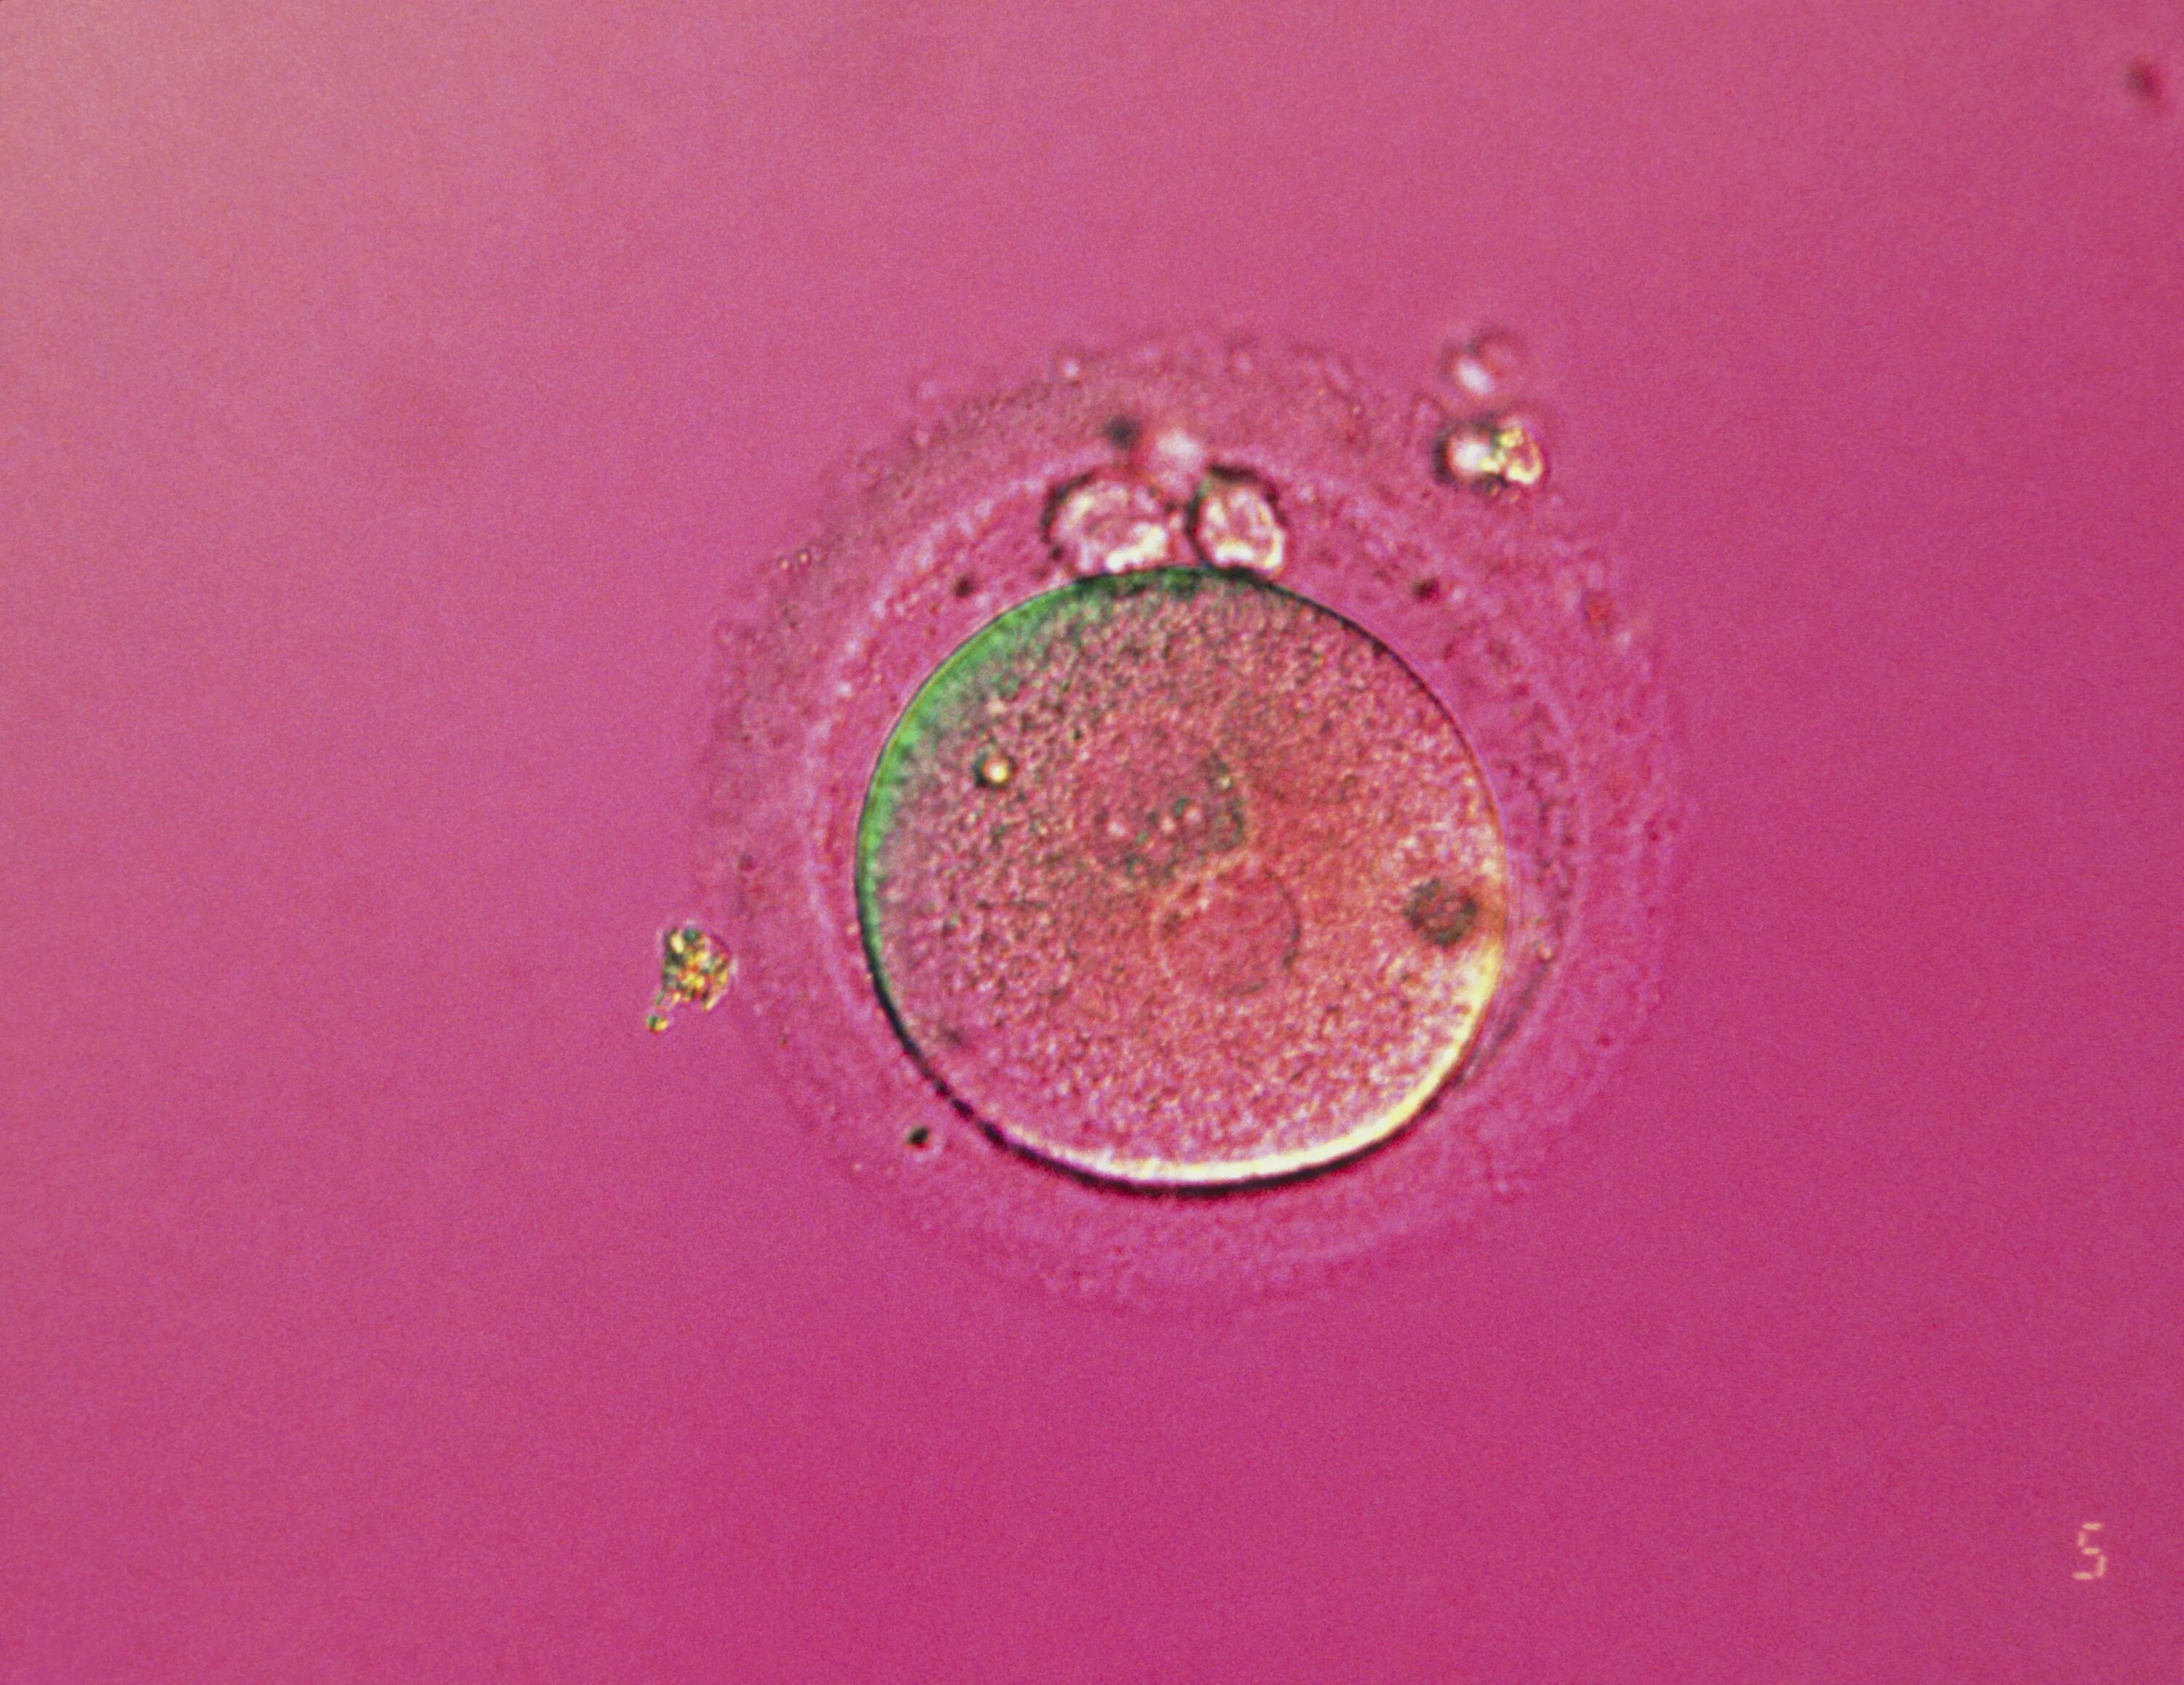

Зигота и яйцеклетка